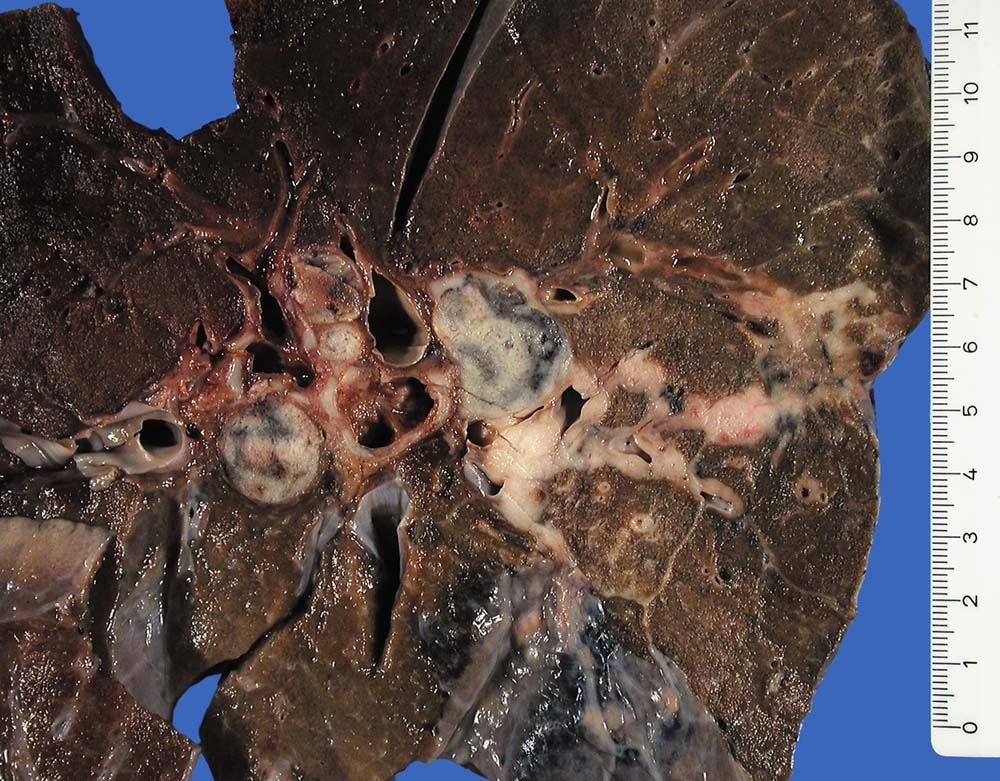

Kleinzellige Karzinome entwickeln sich bevorzugt zentral.

Pathologischer Befund